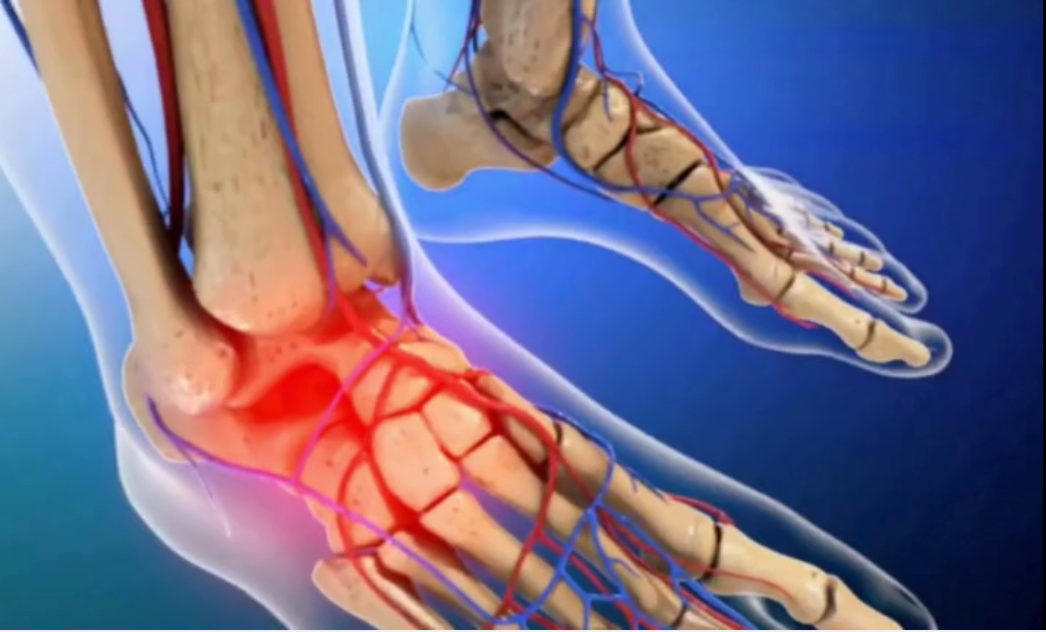

- 3D Dental Animation for procedures like cleaning, cavity filling, root canals, etc.

- Detailed oral health explainer videos that are engaging and easy to understand

I have extensive experience in dental visualization and animation, ensuring that every project is accurate, professional, and visually appealing. I use advanced software to deliver high-quality videos tailored to your specific needs.

Tagged : 3d dental animation, 3d medical animation, dental models for oral health explainer, surgical animation, tray whitening